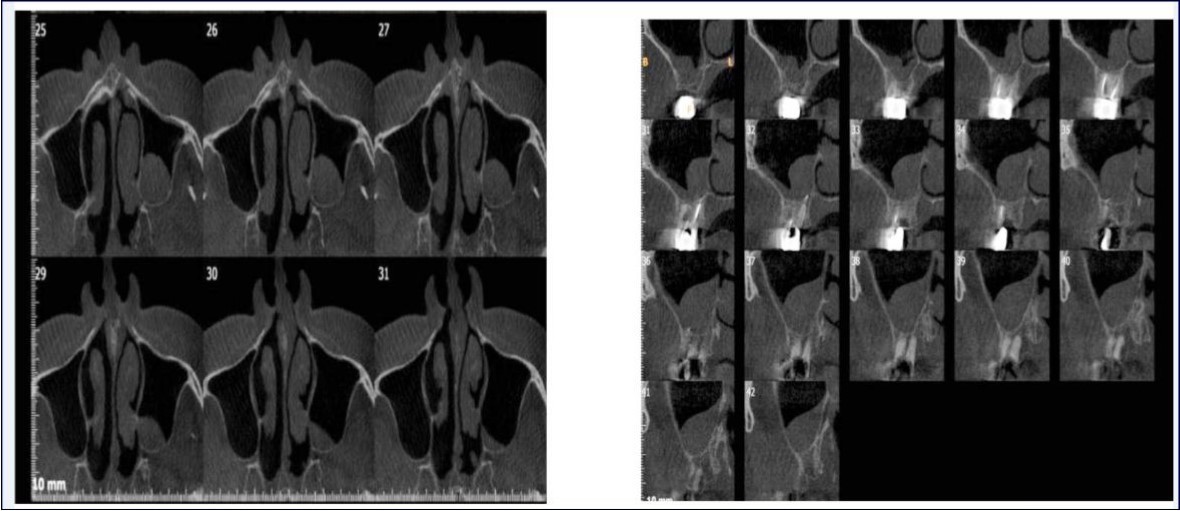

Sinus augmentation procedures were carried-out in 17 patients seeking implant options for oral rehabilitation including 10 for direct and 10 of indirect procedures (n=20, 10 direct and 10 indirect). The study comprised of 43% females and 57% males with a mean age of 46.07 years. A total of 17 patients (20 segments) satisfying the above criteria requiring placement of implants in atrophic maxilla/ increased pneumatisation of the maxillary sinus were selected for the study. The patients were informed about the study including the use of the synthetic graft material and their approval was sought before their inclusion in the study. A written informed consent was obtained from each of the participating patients. For each patient, a detailed case history was taken including chief complaint, history of presenting illness and medical history and personal history. A thorough clinical examination, including systemic and regional examination, was done. Patients with sinus pathology, previous sinus surgeries, chronic smokers, patients under 18 years of age, and with underlying systemic conditions which contradicts any surgical procedures were excluded from the study. The type of sinus lift was decided based on the pre-operative residual bone height evaluated radiographically. The residual bone height was recorded using CBCT scan and a computer based software where the measurements were made from the crest of the ridge till the sinus floor lining. Indirect sinus augmentation was done in patients with a bone height of <9mm but more than or equal to 5mm. Patients with a bone height of less than 5mm were taken up for direct sinus augmentation. The period of edentulousness varied from 6 months to 12 months. Apically tapered, commercially pure titanium implants (Life Care Devices Private Limited Mahim, West Mumbai, India) were used for patients undergoing indirect sinus augmentation. The length of implant was 8, 10, and 11.5 with diameters of 3.5, 4.0, and 5 mm respectively. Patients in the category of direct augmentation underwent the lateral approach procedure and augmentation with an alloplastic graft material. Implant placement was done after 6 months as the second stage procedure. The patients were assessed clinically at immediate post-operatively, and at 1 week, 1 month, 3 months, and 6 months post-operatively. Radiographic assessment for bone height was done pre-operatively and at 6 months post-operatively using cone beam computer tomography. In this comparative study, the measurements were tabulated and statistically analyzed to evaluate the difference in increase in bone height between direct and indirect sinus augmentation procedures radiographically. Orthopantomographs (screening tool) were taken to rule-out other pathologies and as a part of initial assessment. CBCT scans were assessed for pre-operative and post-operative bone height, bone width and bone density. The CBCT scans were obtained from Kodak 9300 which is a hybrid machine using a CS3D imaging software and flap panel detector sensor with exposure parameters of 90 KVp and 10 mA and resolution of 90 microns. The cross sections were made 1mm apart. (Image 1, Image 2, Image 3) The bone height measured pre-operatively using CBCT considered the pre-operative bone height as a measurement taken from the crest of the ridge till the sinus floor and post-operatively, from the crest till hyper-density evident apically. These measurements were standardized as a computer software drawing tool was used. Bone width was taken as the bucco-palatal width at three intervals- at the crest, 3mm from the crest and 6mm from the crest. Bone density was assessed visually by the width of trabecular pattern and were classified based on Misch‘s classification.4 Another additional bone density tool used was the pixel values (the gray scale values) obtained on the CBCT scan, although not reliable, and comparison done pre-operatively and post-operatively. The pixel values contained were a mean of three measurements obtained along the residual bone corresponding with the bone width levels.

Image 1.Routine sequential CBCT scans A and B) Axial sections; C) Cross section; D) Oblique sagittal section; E) 3-D reconstruction; F) Width measurement

Image 2.Axial section of CBCT showing sinus septae

Image 3.Axial sections of CBCT showing sinus mucosal thickening